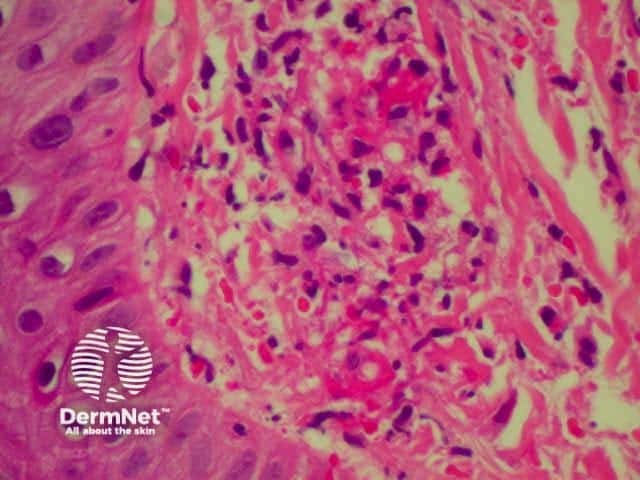

Systemic vasculitis may affect the skin and vascular damage may be the main feature or a secondary feature in several skin diseases. Link to a clinical description of cutaneous vasculitis.

The histological features they have in common are:

Leucocytoclastic vasculitis Leucocytoclastic vasculitis